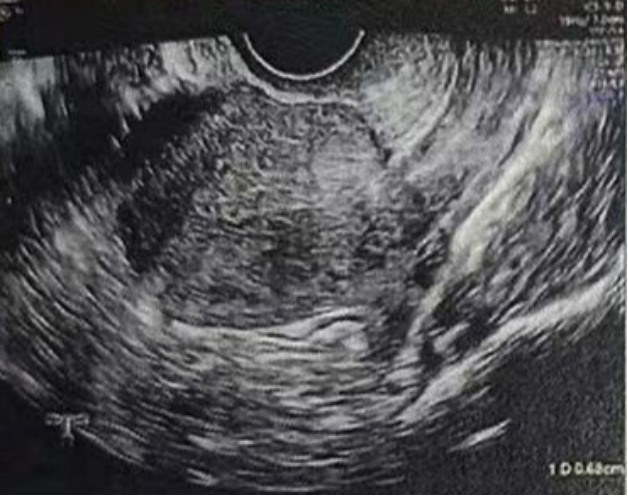

子宫内膜厚度:4.6 毫米,子宫有瘢痕大小 0.76*0.19 厘米

雌二醇:241 pg/mL

孕酮:0.13 ng/ml

子宫内膜厚度:9.3-10 毫米

- 有粘液滞留在腔内,从峡部瘢痕延伸至子宫底

- 双卵巢无囊肿

- 计划在胚胎移植前重复超声检查以冲洗峡部瘢痕

• Pre-Irrigation灌洗前: